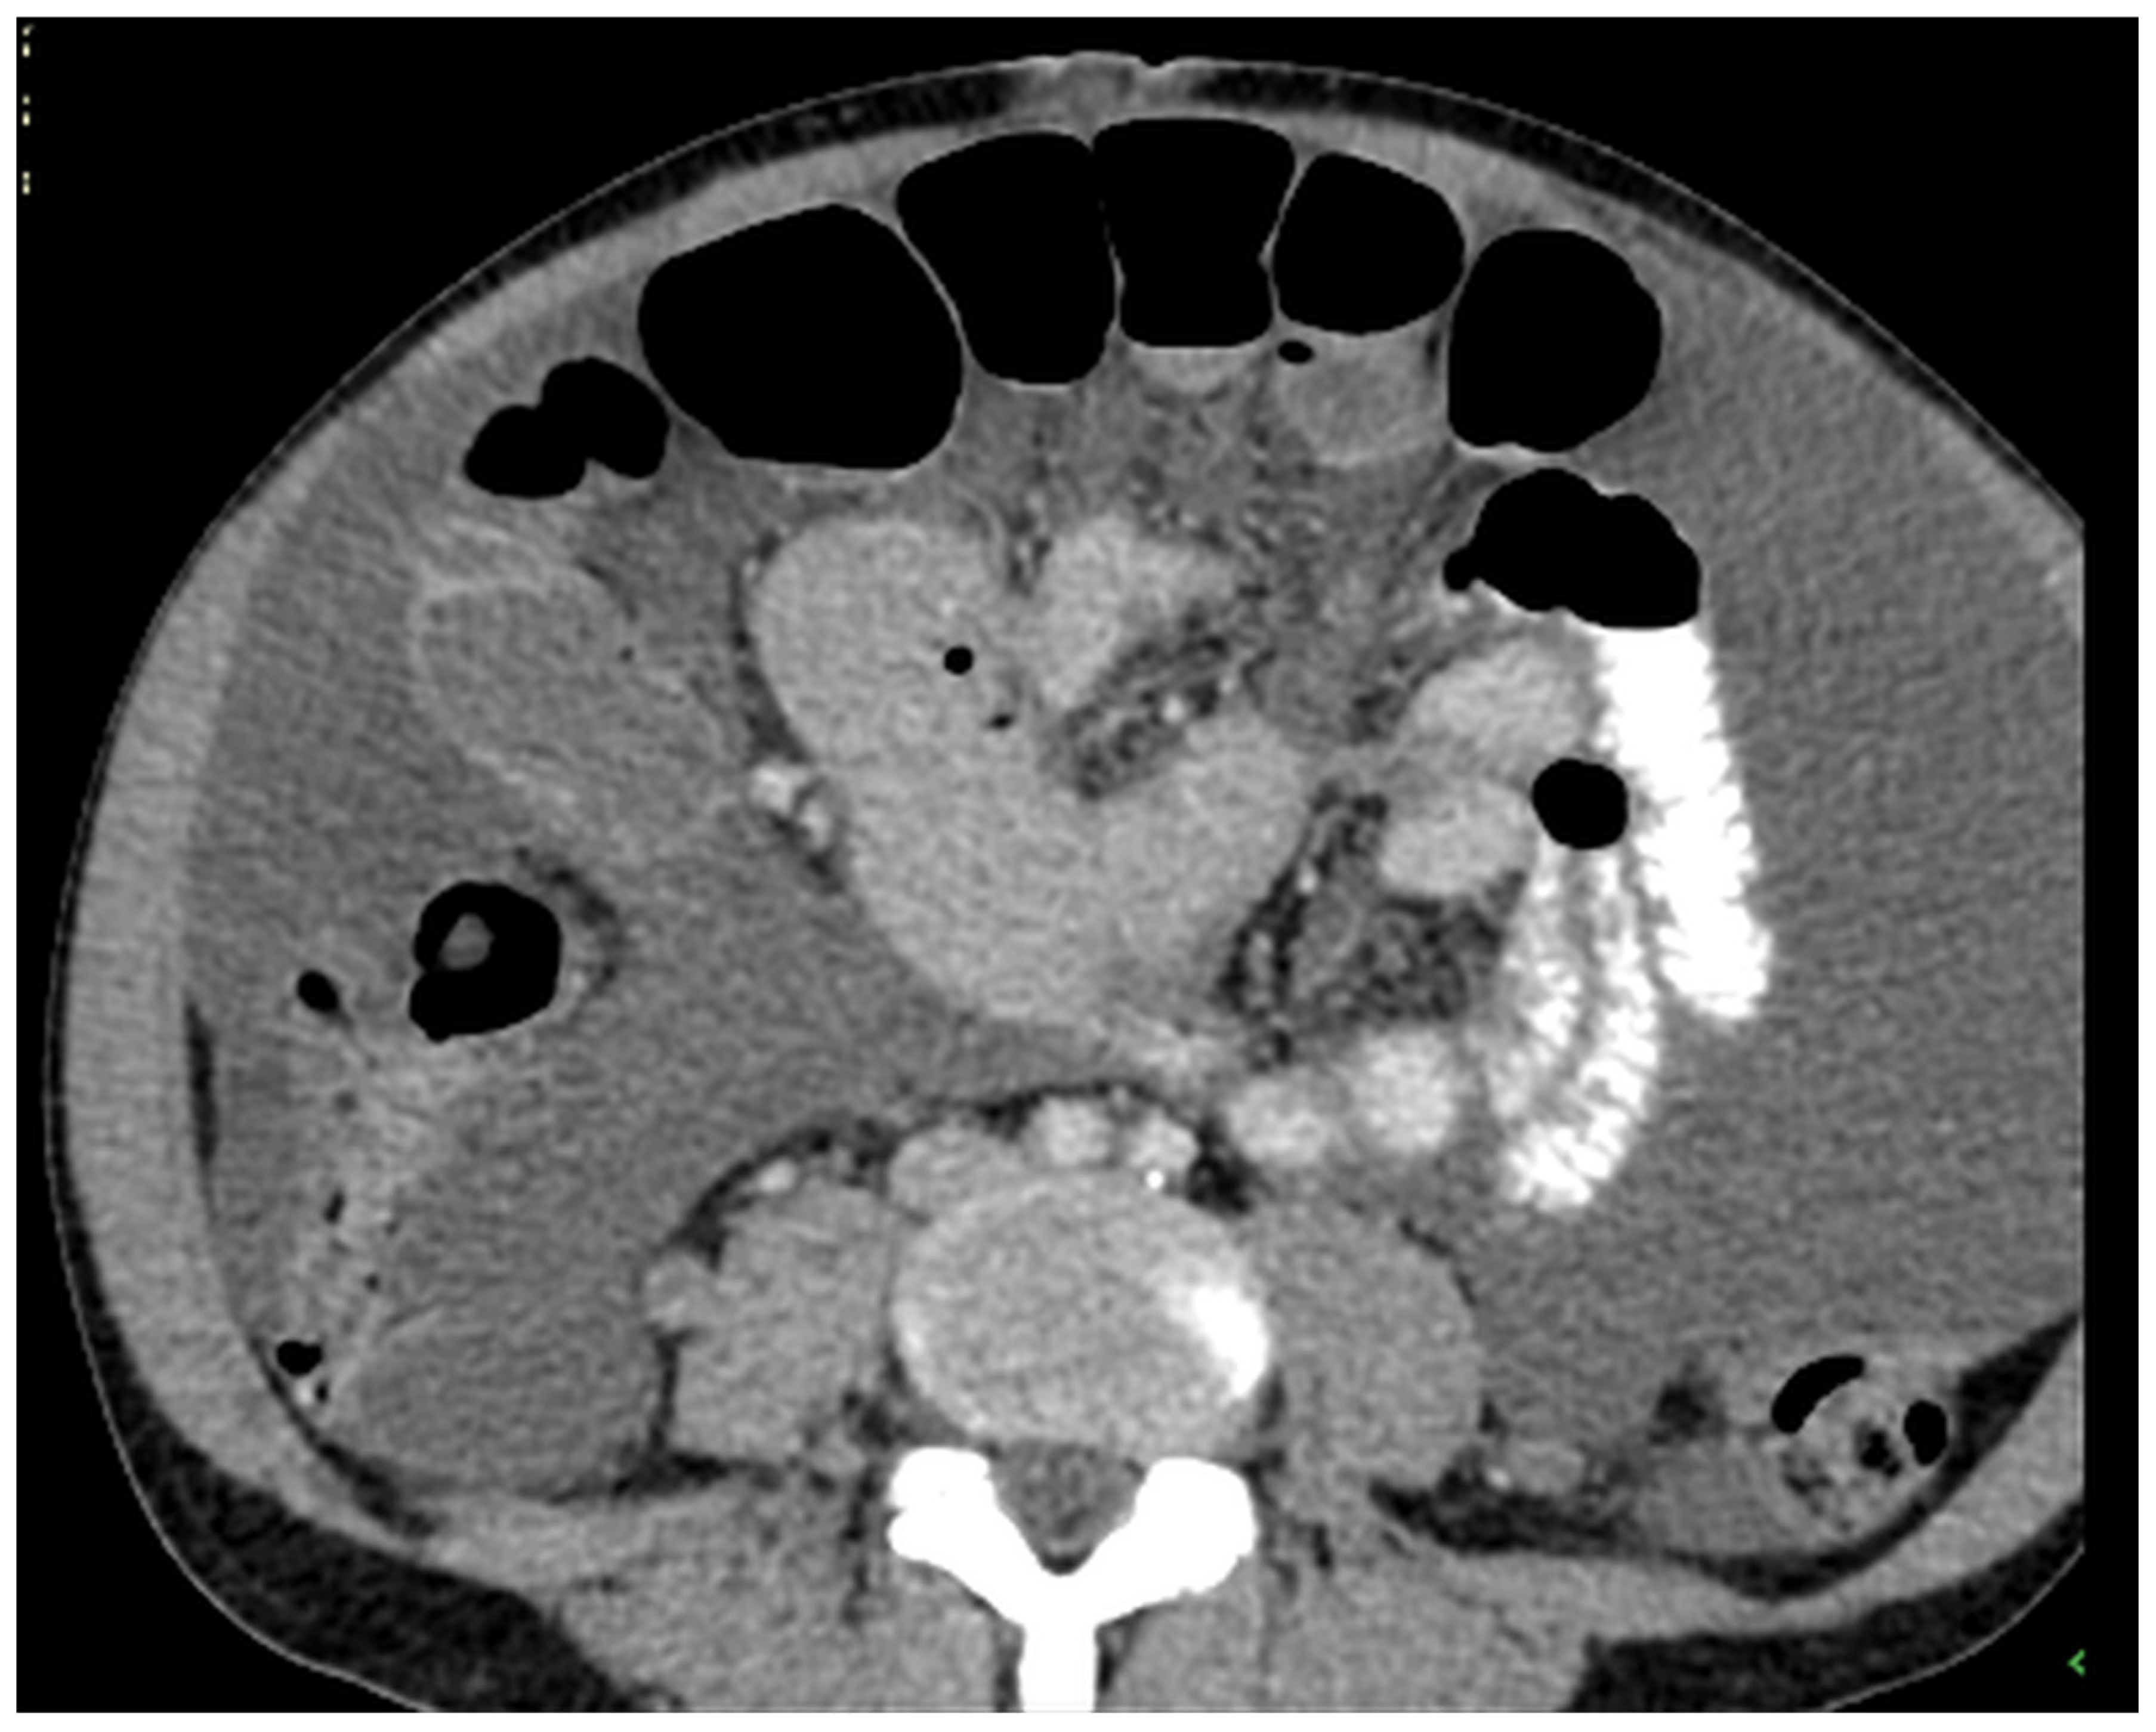

Figure 13. CT, venous phase, axial plane.

Figure 11, Figure 12, Figure 13, Figure 14 and Figure 15. Advanced stage of the disease. The abdomen is full of tumors and mucin. Typical signs are heterogeneous or hypodense masses in the form of lobules often with septa, which could be enhanced by contrast and could be associated with calcifications.

Patients with a misdiagnosed rupture of the mucocele may develop pseudomyxoma peritonei. It is characterized by the presence of an abundant gelatinous substance in the abdomen. Diffuse, progressive, and abundant mucin-containing tumor cells are typical of this disease [2] (Figure 11, Figure 12, Figure 13, Figure 14, Figure 15 and Figure 16). The interval between rupture and advanced disease is several years. In our clinical series, the interval was about 5 years. In the literature, we found a wide range of this interval from 12 months to 10 years [9,10]. The natural history of PMP revolves around the “redistribution phenomenon”, whereby mucinous tumor cells accumulate in the Douglas pouch, in the diaphragm (more on the right), and the small and large omentum (Figure 17). The small intestine is less involved [4]. Pseudomyxoma peritonei is a slowly progressing disease, which fills the peritoneal cavity over time. There are several classifications of pseudomyxoma. The most commonly used is the PSOGI classification [2]. Mucinous accumulation progresses to malnutrition, bowel obstruction, and respiratory compromise. Rarely, the tumor may spread to the pleural cavity. This has been described in 5.4% of cases. It may occur spontaneously or as a result of diaphragmatic injury during cytoreduction [8,11].